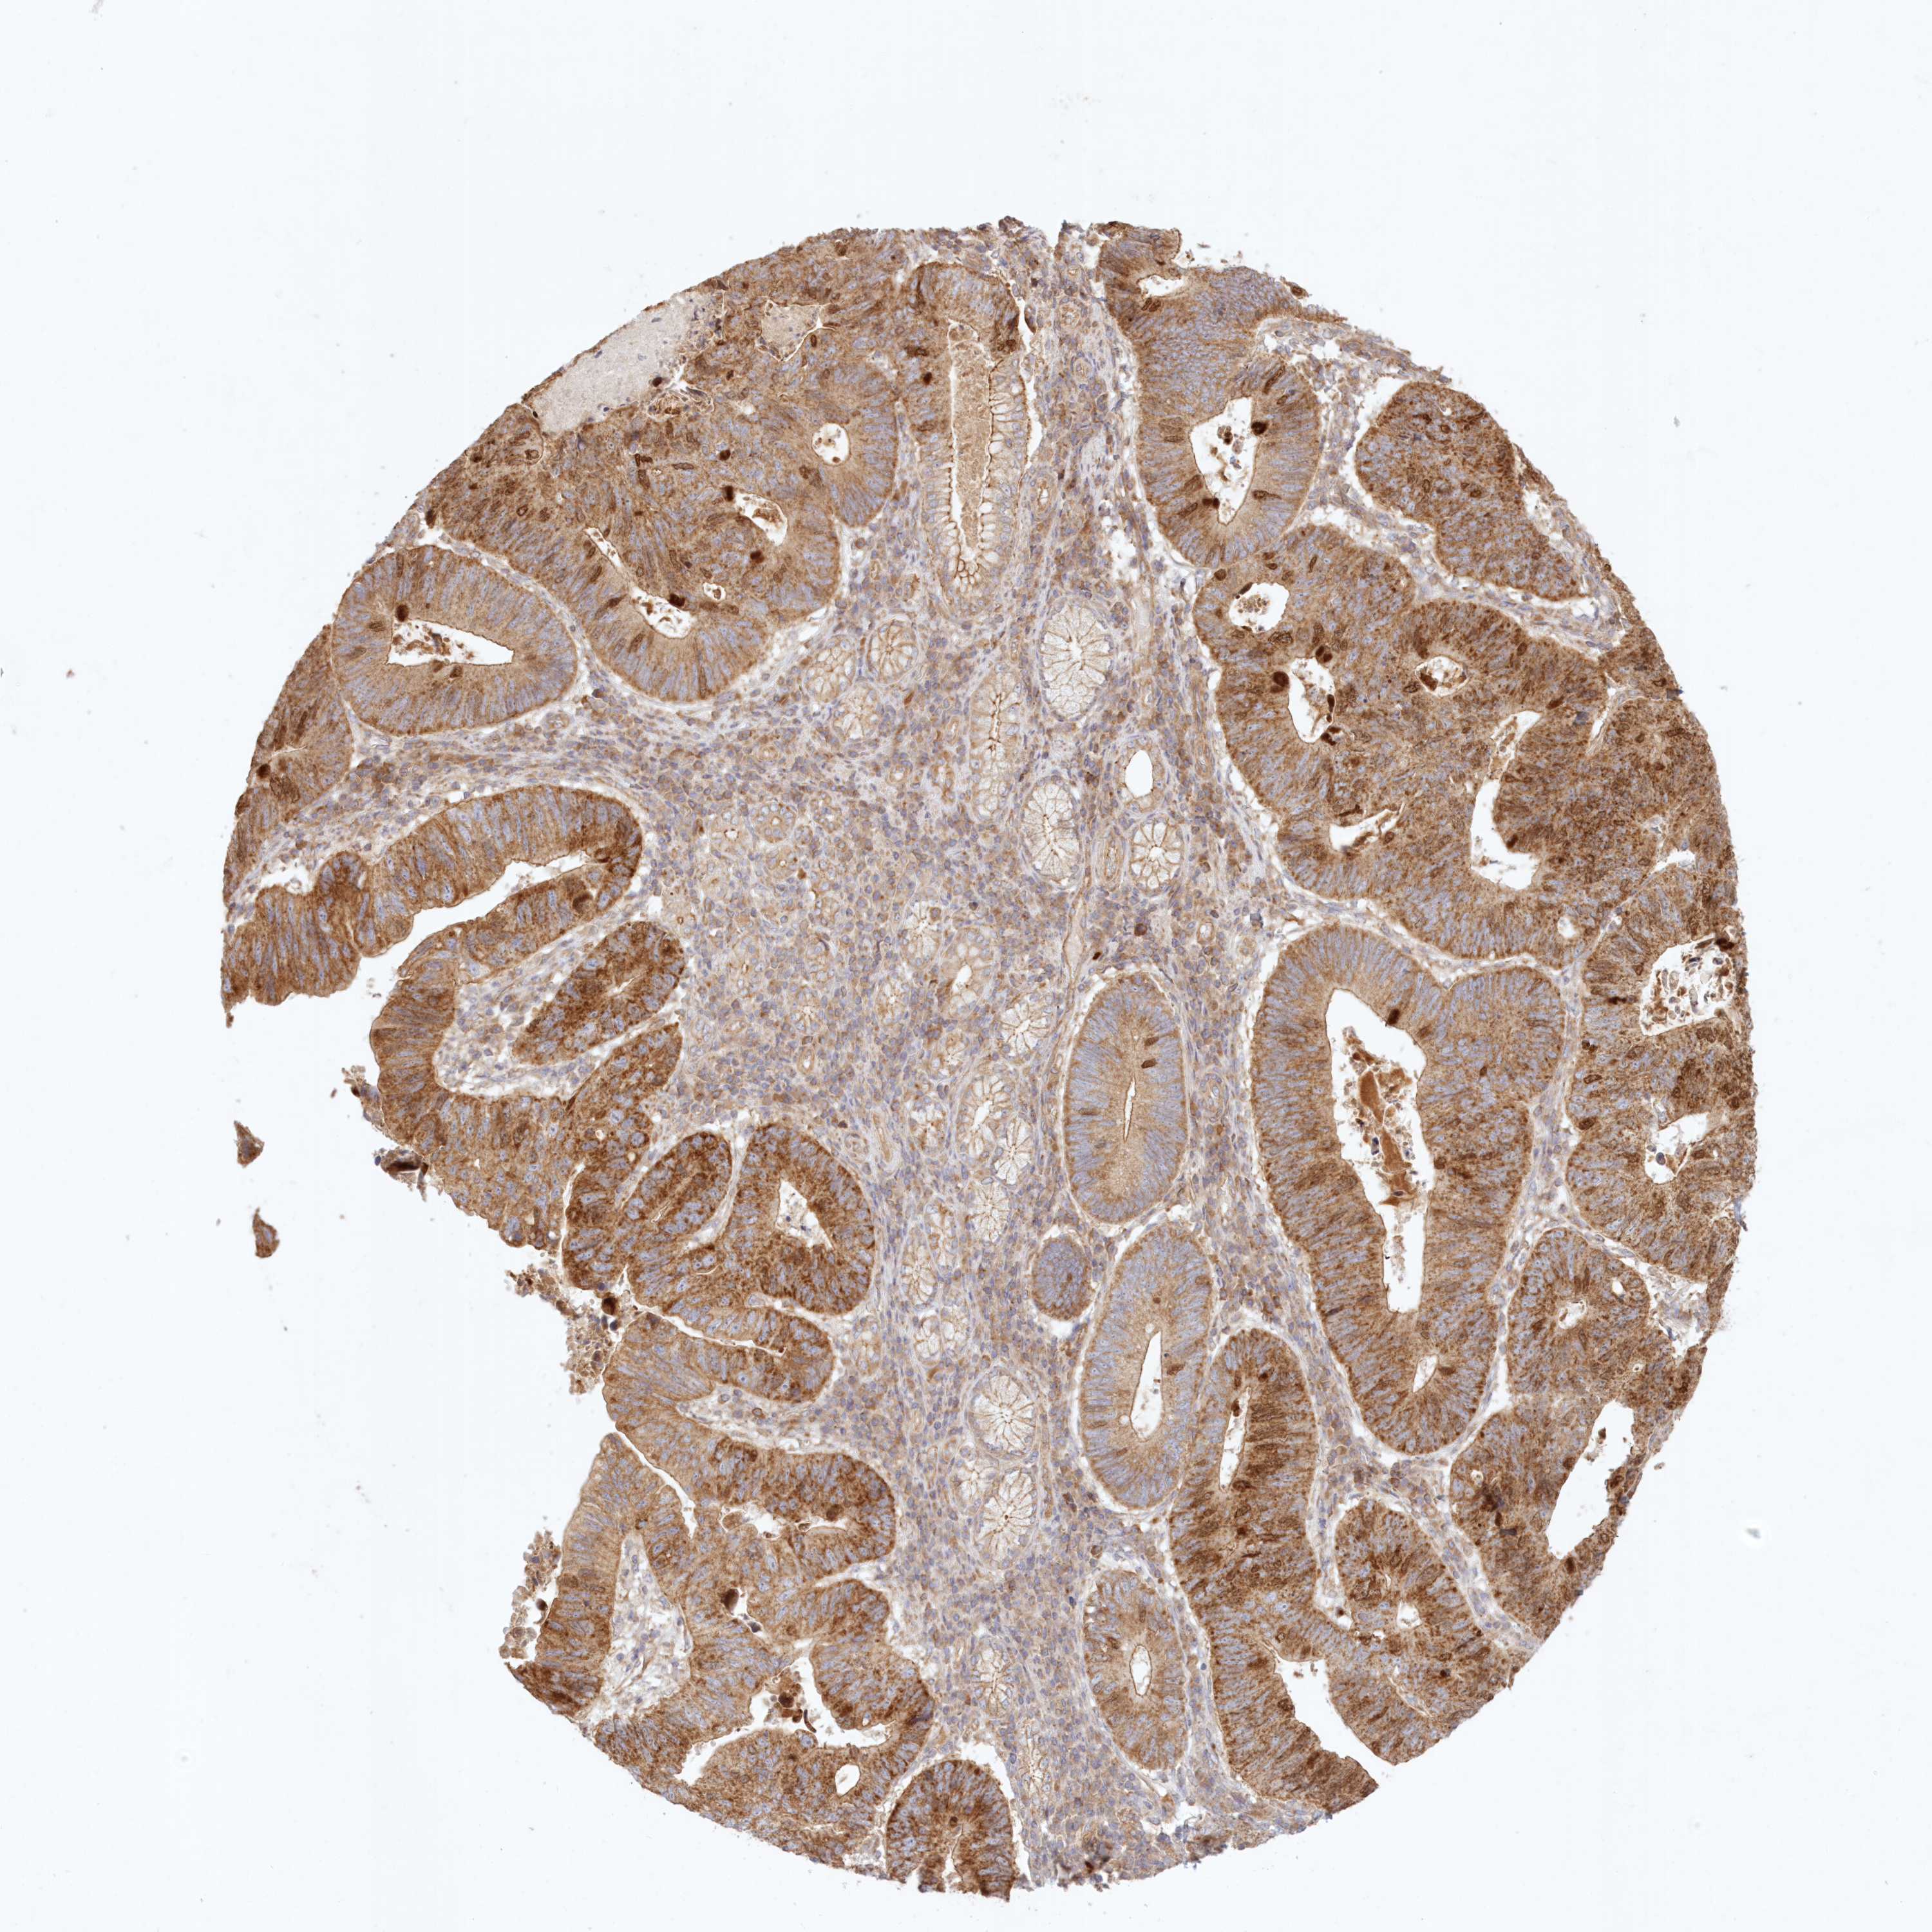

STOMACH CANCER - Protein expressioni

A mouse-over function shows sample information and annotation data. Click on an image to view it in a full screen mode. Samples can be filtered based on level of antibody staining by selecting one or several of the following categories: high, medium, low and not detected. The assay and annotation is described here.

Note that samples used for immunohistochemistry by the Human Protein Atlas do not correspond to samples in the TCGA dataset.

Antibody stainingi

Antibody staining in the annotated cell types in the current human tissue is reported as not detected, low, medium, or high, based on conventional immunohistochemistry profiling in selected tissues. This score is based on the combination of the staining intensity and fraction of stained cells.

Each image is clickable and will lead to virtual microscopy that enables deeper exploration of all samples and also displays staining intensity scores, fraction scores and subcellular localization as well as patient and tissue information for each sample.

Antibody HPA036891

Antibody HPA036892

Antibody HPA061498

Staining

High

Medium

Low

Not detected

Intensity

Strong

Moderate

Weak

Negative

Quantity

>75%

75%-25%

<25%

None

Location

Nuclear

Cytoplasmic/membranous

Cytoplasmic/membranous,nuclear

Adenocarcinoma, NOS